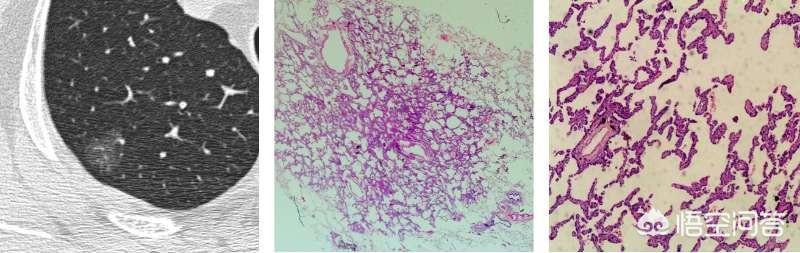

Typischerweise sind atypische adenomatöse Hyperplasie-Läsionen kleiner als 5 mm und relativ selten größer als 8 mm. Unten sehen Sie ein CT und die Pathologie einer 8 mm großen atypischen adenomatösen Hyperplasie.

Für Schliffknötchen, bei denen keine chirurgische Möglichkeit gesehen wird oder die sich im Stadium der atypischen adenomatösen Hyperplasie befinden können.Welche Erkrankungen in der Nachsorge erfordern eine sofortige Operation?? Der Filmleser sollte die Läsionen vorher und nachher sorgfältig vergleichen, und wenn sie sich alsDie Läsion ist etwas größer als die vorherige Läsion oder sogar etwas dichter, oder es wird festgestellt, dass ein Blutgefäß in die Läsion hineingewachsen ist.Auf dem Bild unten ist es zum Beispiel Zeit für eine Operation.